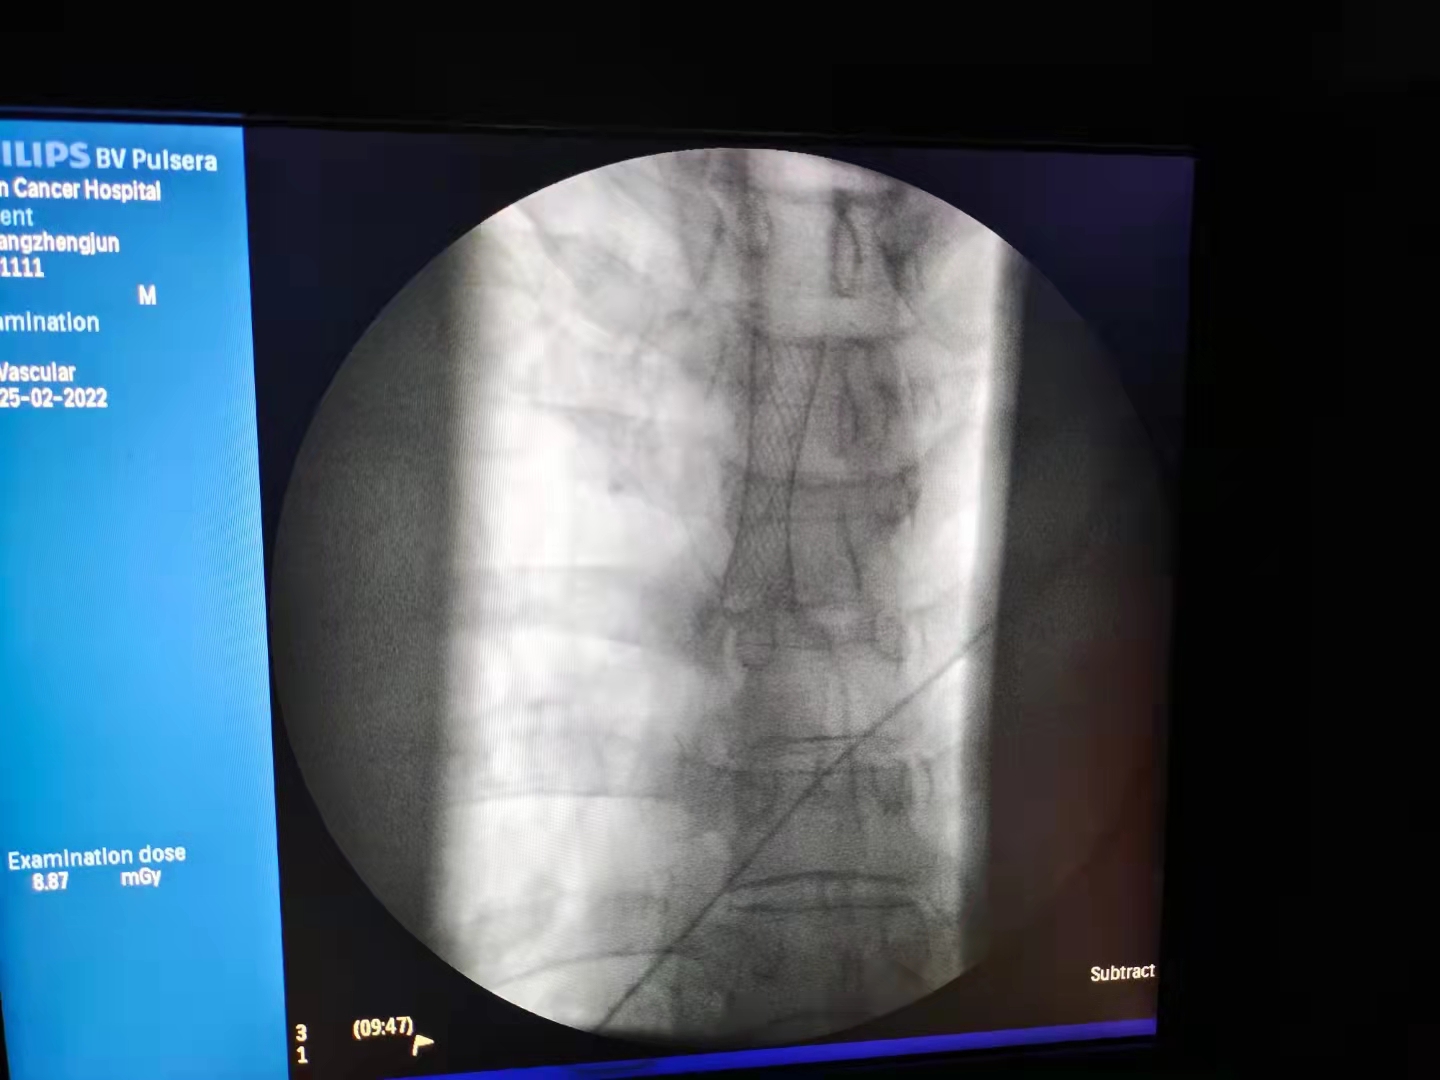

最近接诊了一位67岁食管癌晚期患者曾爹,他曾做过放化疗,近期因食管癌肿瘤侵犯并压迫气管,导致气管重度狭窄,呼吸困难。

#微创手术解决危重问题#实施气管支架植入术后,曾爹立即感觉呼吸顺畅,咳痰症状明显缓解,整个过程约半个小时。 随后曾爹由护士送入病房,途中正常交流,没有呼吸困难。

其实曾爹的微创手术风险挺大,肿瘤除了压迫气管外,也让他的食管狭窄,目前靠胃管进食,身体状态情况很差,还伴有电解质紊乱。还好气管支架植入成功,为曾爹下一步治疗提供了良好机会。

下一步根据曾爹身体情况,将尽快置入食管支架,解决进食,保证身体营养,为后续抗肿瘤治疗奠定基础。